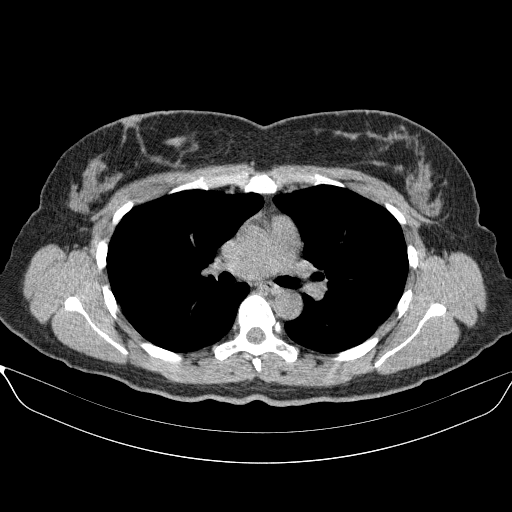

Image Grid

4Γ—3 grid: Rows show different image types (Original NATIVE, Reconstructed NATIVE, Original VENOUS, Generated VENOUS), Columns show windowing techniques (No Window, Lung Window, Mediastinum Window)

Original NATIVE CT scan (input)

Full window (WL 1023.5, WW 4095 β†’ Low βˆ’1024, High +3071)

Generated VENOUS CT scan (A→B translation)